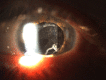

Diabetes mellitus (DM) is a chronic systemic disease that has increases in prevalence over time. DM can affect all ocular structures, with cataract being the most common ocular complication. Cataract is the leading cause of blindness worldwide. Due to several mechanisms, there is an increased incidence of cataract formation in the diabetic population. Advancements in technology have now made cataract surgery a common and safe procedure. However, the diabetic population is still at risk of vision-threatening complications, such as diabetic macular edema (ME), postoperative ME, diabetic retinopathy progression, and posterior capsular opacification.